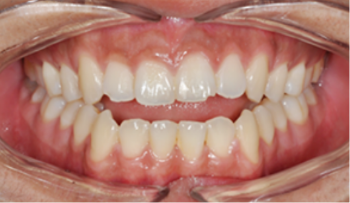

첫 내원(초진)

치아와 안모에 대한 임상검사를 합니다.Orthodontics

치아와 안모에 대한 임상검사를 합니다.